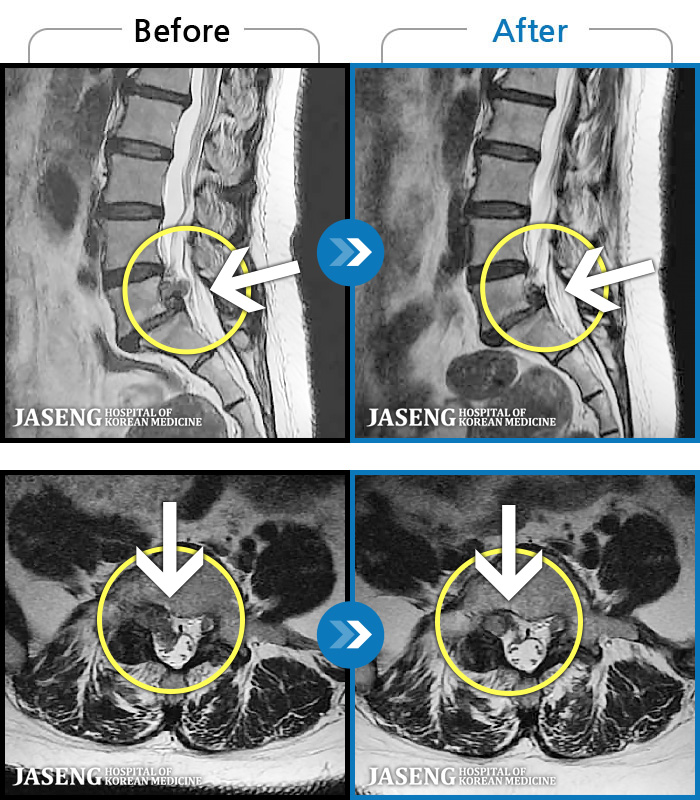

[] 03.04.01~09.11.01